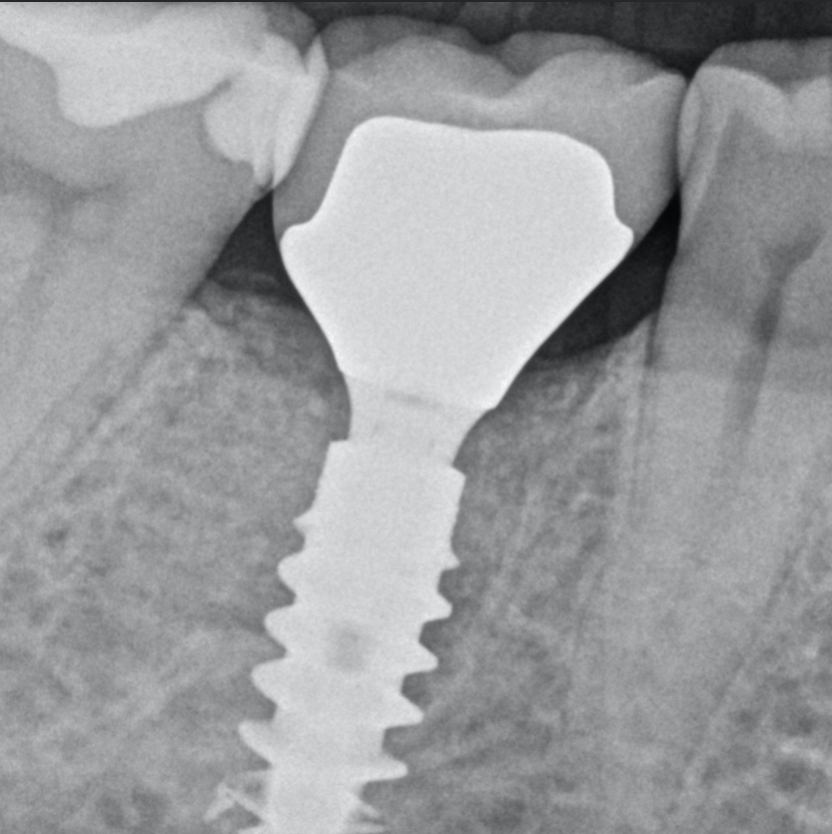

3D positioning

Different types of healing abutments